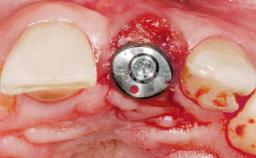

A 30-year-old female patient had lost tooth 21 and was referred to our clinic for consultation and treatment. Due to advanced apical infection, tooth 21 had been extracted two months earlier at another clinic and an acrylic-resin tooth had been bonded to the adjacent teeth. The patient desired implant treatment to avoid any damage to the adjacent natural teeth. While the patient had no history of any systemic disorder, she was a heavy smoker and exhibited medium to advanced periodontitis in the entire jaw. After the initial treatment to achieve a pocket probing depth of less than 4 mm and no bleeding on probing, a decrease in the height of the papillae mesial and distal to the extraction site and overall gingival recession were observed.

Type of Implants One-Piece|Reduced-Diameter

Attachment One-Piece|Reduced-Diameter

Placement Protocol Early or late implant placement